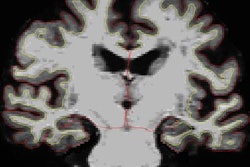

VIENNA - Detailed brain maps compiled from voxel-based morphometry of brain MR images can yield new insights into human cognition, including evidence that the hippocampus has an important role in executive function, according to a Saturday morning presentation at ECR 2017.

A Dutch research team used voxel-based morphometry analysis of MR images and cognitive tests on nearly 4,000 patients and found several positive and negative associations between gray-matter density and cognitive functioning. They also determined that the hippocampus -- known as the most important brain structure for memory -- was important in executive functioning.

As a result, the researchers sought to use voxel-based morphometry to investigate the neural substrate of cognitive function in middle-aged and elderly subjects. They utilized data from the Rotterdam Study, a prospective population-based cohort study of the causes and consequences of age-related disease. The study has run since 1990 and includes 14,926 participants ages 45 and older.

The team performed tissue segmentation on the MR images using software that was developed in house. Next, they performed voxel-based morphometry to calculate local gray-matter density. To explore the association between local gray-matter density and cognitive function, the researchers used linear regression models with voxel values of gray-matter density as the dependent variable; age, sex, education level, and cognitive function were used as independent variables.